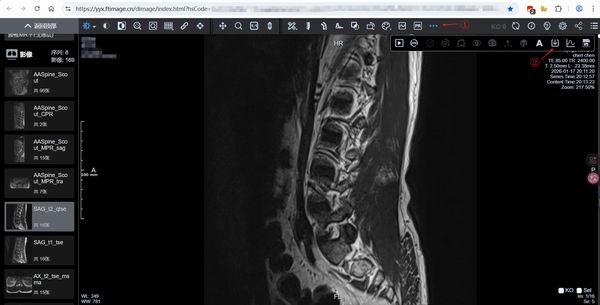

Honker.org.cn红盟网讯 最近去华山医院拍MR磁共振,检查出来后并没有直接打印(另收费),经中医师讲起,在检查单上有二维码,随即扫描后,发现是有图像可以自行查看的。

不过网站可能不能存放太久,为了防止数据被删除,还是希望把资料保存到本地,于是考虑从网站上下载下来,回家后,通过电脑,经过一番折腾,终于把资料下载到本地,这样就相对安心了,下次去中医那就可以给医生看了。

1.进入网址,需要输入身份证的后6位,然后就可以打开自己的检查报告,在左侧下面,就有影像图片。

2.点击一张,点击右上角的...三个点,就会有下载的向下箭头

a.格式选择:选择DCM格式,或者JPG(图片比较小,300需要自己放大,直接用看图类软件就能打开看了)

b.范围:选择检查,这样所有的图片都被保留下来。

3.点了之后,有时候受服务器网络影响,可能不能一下子提供数据下载,会弹出一个框:“正在准备数据,等待一分钟后再试”,点确定后,等会再重新点下载箭头,

如果反复弹出“正在准备数据需要等待一分钟”,那么只能再等会再试,直到出现文件下载,并下载zip。

4.不用解压缩,等会在软件中直接查看zip即可。